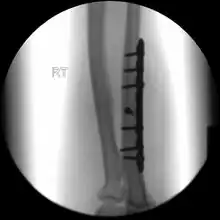

.jpg)

When there is a displaced fracture or when the radioulnar joints are involved an operation is often performed, using either flexible rods or screws and plates in order to reduce the fracture and immobilise the bone.[3]